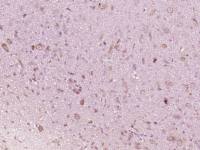

| 产品图片 | ![]() Sample: Placenta (Mouse) Lysate at 30 ug Lung (Mouse) Lysate at 30 ug Primary: Anti-Cytokeratin 7 (bs-1744R) at 1/300 dilution Secondary: IRDye800CW Goat Anti-Mouse IgG at 1/10000 dilution Predicted band size: 54 kD Observed band size: 54 kD ![]() Sample: Large intestine (Mouse) Lysate at 30 ug Primary: Anti- Cytokeratin 7 (bs-1744R) at 1/300 dilution Secondary: IRDye800CW Goat Anti-Mouse IgG at 1/10000 dilution Predicted band size: 54 kD Observed band size: 54 kD ![]() Tissue/cell: human lung carcinoma; 4% Paraformaldehyde-fixed and paraffin-embedded; Antigen retrieval: citrate buffer ( 0.01M, pH 6.0 ), Boiling bathing for 15min; Block endogenous peroxidase by 3% Hydrogen peroxide for 30min; Blocking buffer (normal goat serum,C-0005) at 37℃ for 20 min; Incubation: Anti-Cytokeratin 7 Polyclonal Antibody, Unconjugated(bs-1744R) 1:200, overnight at 4°C, followed by conjugation to the secondary antibody(SP-0023) and DAB(C-0010) staining |